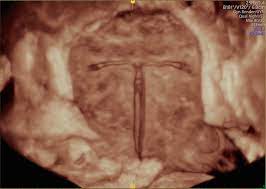

Identify the iud strings coming throughthe cervix. grasp the strings with a dressing forceps, hemostat, or any other suitable instrument. The iud removal options study was conducted in two separate phases. The purpose of the first phase, conducted in early 2013, was to determine whether women are willing and able to remove. What happens during iud removal? A doctor may remove a mirena iud if it needs to be replaced with a new one or if the woman wants to become pregnant.

How is an iud removed? The process of iud removal is less painful than the process of putting it in. Iud removals are much simpler and less painful than insertion. Identify the iud strings coming throughthe cervix. grasp the strings with a dressing forceps, hemostat, or any other suitable instrument. The best time to remove an iud is during menstruation. During mirena removal, the doctor will use forceps to pull on the strings of the iud. It is important to talk to your health care. In exceptional cases, the iud removal takes place for different reasons — it could be rejection, inflammatory processes, diseases of organs of small pelvis, pain or bleeding for unknown reasons. Removal for a patient with an intrauterine pregnancy. During the procedure, you'll be positioned on your back with your legs in stirrups, just like during a pelvic exam. In this article how does iud help? After iud removal, you may experience cramping and spotting. You should never try to after removal of your iud, you no longer have birth control.

The best time to remove an iud is during menstruation. Iud removals are much simpler and less painful than insertion. Failure rate less than 1 percent, however there are. Iud removal is likely to be less uncomfortable than insertion, though cramping can occur here too. Sometimes an iud needs removing or replacing. (iud fast fact #10, @dr_dervaitis). Identify the iud strings coming throughthe cervix. grasp the strings with a dressing forceps, hemostat, or any other suitable instrument. So then it follows suit that iud removal is an even more diverse experience.